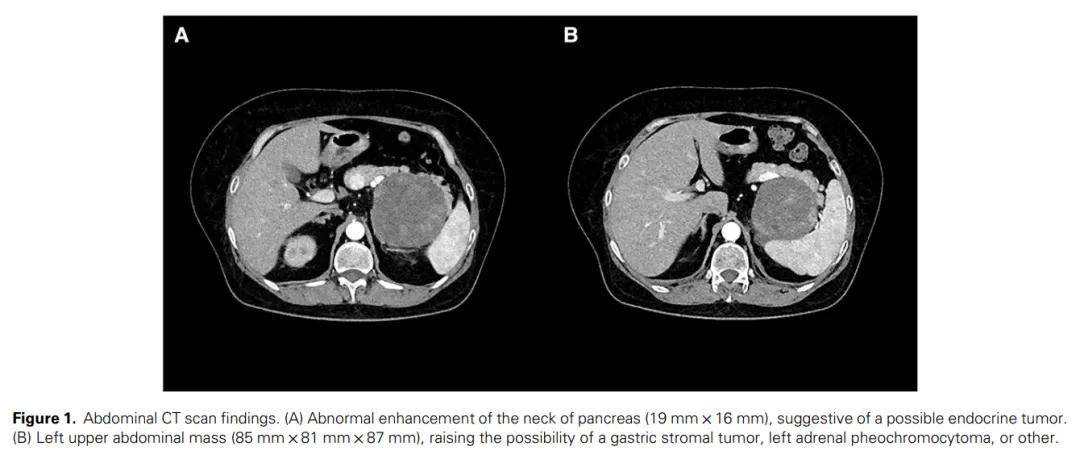

多发性内分泌腺瘤病1型(MEN1)是一种罕见的常染色体显性遗传性疾病,以甲状旁腺、胰岛和垂体前叶的肿瘤形成为特征。本文报道了一个家族病例,其中先证者于 25 年前被诊断为泌乳素瘤。在本次住院期间,该患